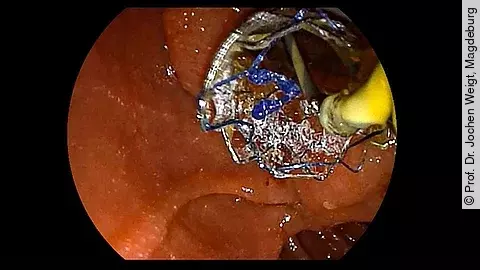

Endoskopisches LehrvideoStentwechsel mit Soehendra Stent-Retriever

Wie wechselt man einen Stent achsgerecht mit einem Soehendra Stent-Retriever? Die hierzu notwendigen Schritte zeigt Ihnen Prof. Dr. Jochen Weigt im Video. Zudem erläutert er, wann diese Technik angewendet wird.